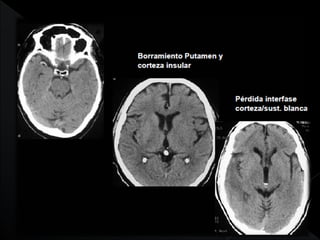

   TAC exámen de elección

DESCARTA O CONFIRMA HEMORRAGIA

• Isquémico :

– Hiperagudo <12 hrs.

– Agudo 12-24 hrs.

TAC~ 50-60% normal

Signos precoces : hiperdensidad arterial,

borrosidad lenticular, banda insular, interfase

grisblanca